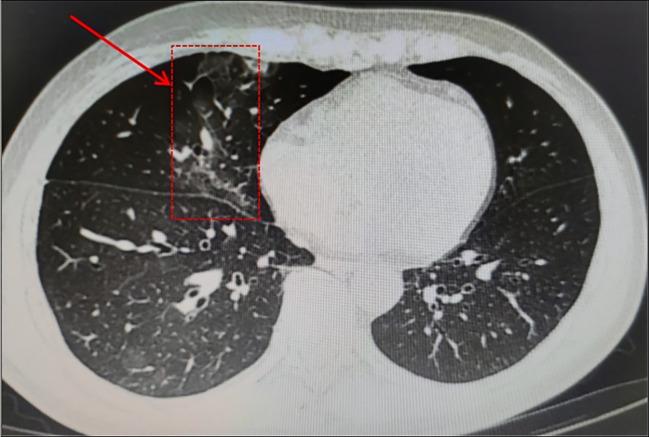

Patients with hematologic malignancy had the possibility of persistent infection with COVID-19, particularly those who received anti-CD20 monoclonal antibody therapy for lymphoma, regardless of vaccination status. We report two cases of follicular lymphoma (FL) infected with Omicron virus that could not be confirmed by routine SARS-CoV-2 tests during maintenance therapy with an anti-CD20 agent, obinutuzumab or rituximab. In addition to immunomodulatory drugs, both of them took Simnotrelvir/Ritonavir to effectively alleviate the symptoms. The aim is to highlight the complexity of SARS-CoV-2 infection and to discuss why it is easy to be infected with COVID-19 for a long time in this fragile patient population and the response to such patients with unexplained respiratory symptoms during maintenance therapy. Patients with hematologic malignancies treated with anti-CD20 agent are at considerable risk of a prolonged disease course and recurrence of COVID-19. Specialized prevention, diagnostic and therapeutic strategies should be developed for this group of patients.

血液系统恶性肿瘤患者有持续感染新冠病毒的可能性,尤其是那些接受抗CD20单克隆抗体治疗的淋巴瘤患者,无论其疫苗接种状况如何。我们报告了两例在使用抗CD20药物奥妥珠单抗或利妥昔单抗维持治疗期间感染奥密克戎病毒的滤泡性淋巴瘤(FL)病例,这些病例通过常规的新冠病毒检测无法确诊。除免疫调节药物外,两人均服用了奈玛特韦/利托那韦以有效缓解症状。目的是强调新冠病毒感染的复杂性,并讨论为何在这一脆弱患者群体中容易长期感染新冠病毒,以及在维持治疗期间对出现不明原因呼吸道症状的此类患者的应对措施。接受抗CD20药物治疗的血液系统恶性肿瘤患者有新冠病程延长和复发的相当大风险。应为这组患者制定专门的预防、诊断和治疗策略。